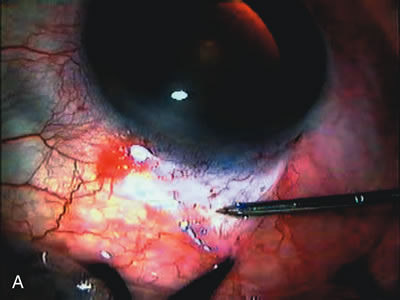

Fig. 4. Viscocanalostomy with deep sclerectomy and phacoemulsification. Nonpenetrating filtration procedures (NPFS) may be combined with phacoemulsification. Patients with mild disc damage and a history of limited topical drug therapy are the best candidates. Patients who require an IOP in the low teens are not good candidates for NPFS. By definition, NPFS is designed to lower IOP without penetrating into the anterior chamber, thereby avoiding the complications associated with trabeculectomy. Viscocanalostomy is intended to allow aqueous to percolate through a trabeculodescemetic membrane into a subscleral cavern created by the deep sclerectomy. The aqueous diffuses from the cavern into the dilated ostia of Schlemm's canal and into the episcleral venous plexus. A. Fashion a uniform 300-micron superficial scleral flap 1 mm into clear cornea. B. Construct a second 600-micron deep flap that facilitates the unroofing of Schlemm's canal, seen as the darker area. C. Use viscoelastic to dilate the ostia of Schlemm's canal. The major problem with viscocanalostomy is the eventual closure of the ostium decreasing flow to the episcleral plexus. D. Dissect the deep flap anteriorly into clear cornea creating the trabeculodescemetic membrane. This membrane is clearly seen between the scleral spur and the bend of the deep flap. The integrity of this membrane ensures the nonpenetrating portion of the surgery. Another problem with NPFS is the eventual fibrosis of this initially transparent membrane requiring goniopuncture. E. Deep sclerectomy gets its name from removal of the deep flap. Removal of this flap creates the potential subscleral space for accumulation of aqueous before it enters Schlemm's canal and exits the episcleral venous plexus. After removal of the deep flap, the superficial flap is sutured into place and conjunctiva closed. Approximately half of these procedures develop a shallow bleb.